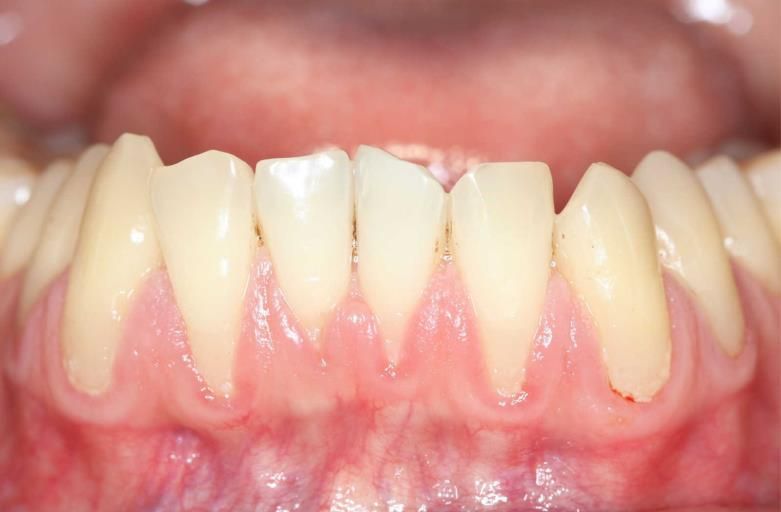

Parodontie

La maladie des gencives et d’os qui entourent les dents est très fréquente dans la population, notamment parce que les patients conservent leurs dents plus longtemps. Des nettoyages fréquents préviennent la maladie, mais dès l’apparition des premiers signes et symptômes, un traitement parodontal devrait être fait. Certaines maladies systémiques augmentent le risque de la parodontite, le diabète étant la plus commune. Si vos gencives saignent ou que vous avez de la sensibilité dentaire généralisée, consultez-nous pour savoir si vous êtes atteint de la parodontite.

Greffes gingivales

Nous procédons à des

greffes gingivales autogènes, ce qui signifie que le patient est le donneur et le receveur des tissus. Si vous avez une gencive mince et des récessions gingivales, un tel traitement pourrait être nécessaire.